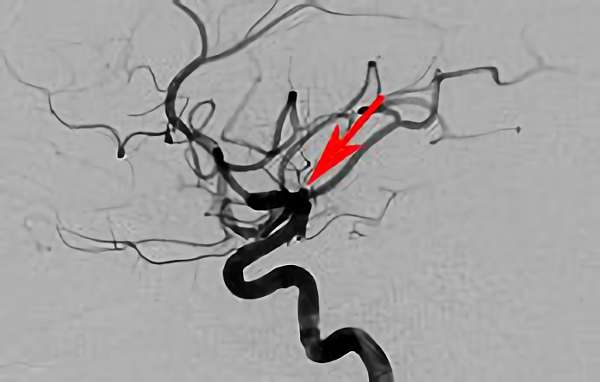

No.1631 手術後